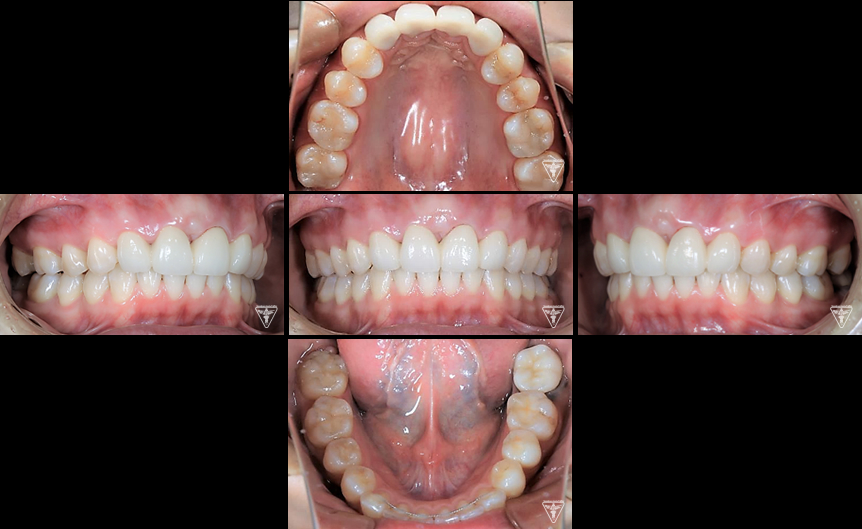

治療後